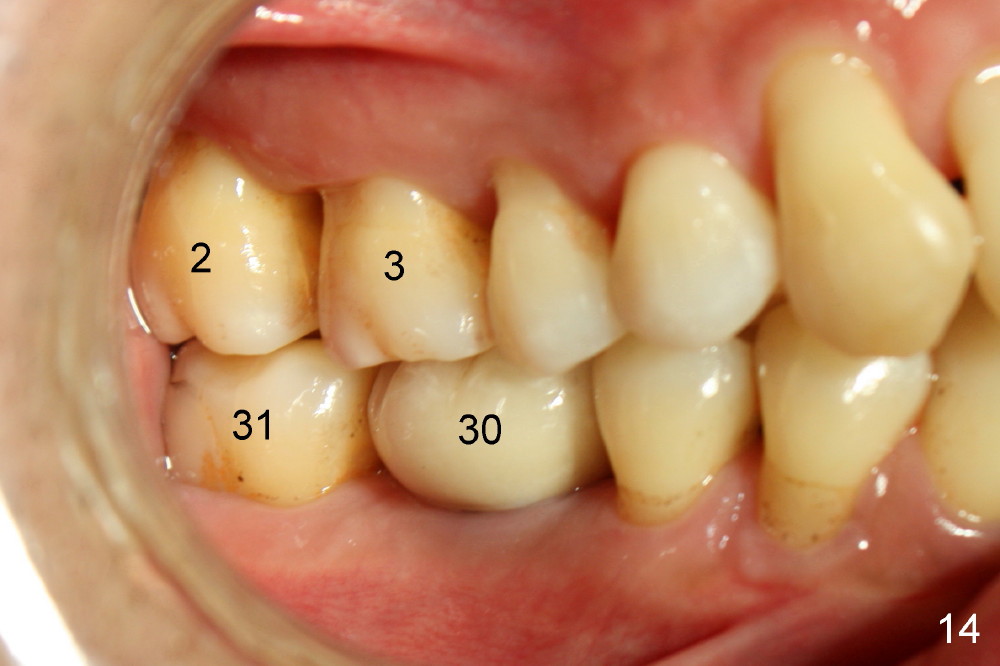

Fig.12-16 are taken 9 months after the orthodontic treatment. The lamina dura appears to form mesial and distal to the implant at the site of #30 (white arrowheads). There is no gross bone resorption associated with orthodontically moved teeth (Fig.12,13: #2,3,31). The posterior overjet remains normal (Fig.14). The arrowheads in Fig.15 indicate a worn facet, which was caused by the previous abnormal overjet (Fig.2). The alignment of the upper right quadrant also remains normal. The patient wears suction down retainers. He is pleased with improvement of mastication.